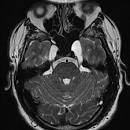

Lymphoma. Axial T2 (a), axial C+ (b), CT (c). Bilateral CN VI palsy and right facial pain. Mottled appearance of clivus and petrous apices on CT—caused by T2 hypointense, enhancing infiltrating lesion. Post treatment (d, e)—complete resolution